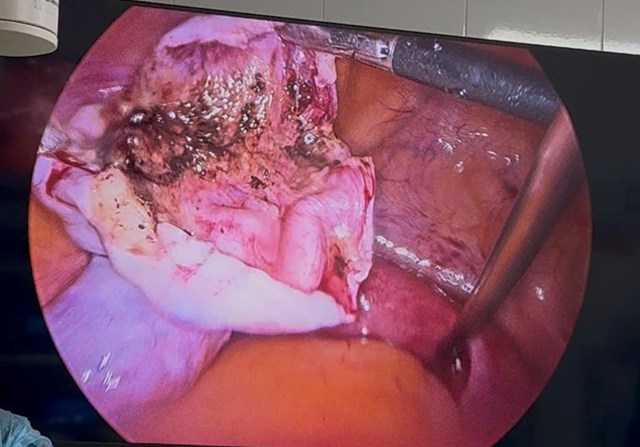

🔬 Trong mổ ghi nhận:

• Buồng trứng trái có khối u ~11cm

• Cuống xoắn 1 vòng, màu tím nhạt (dấu hiệu giảm tưới máu)

📌 Khối u có đặc điểm điển hình của u bì buồng trứng: chứa dịch bã đậu, lẫn tóc